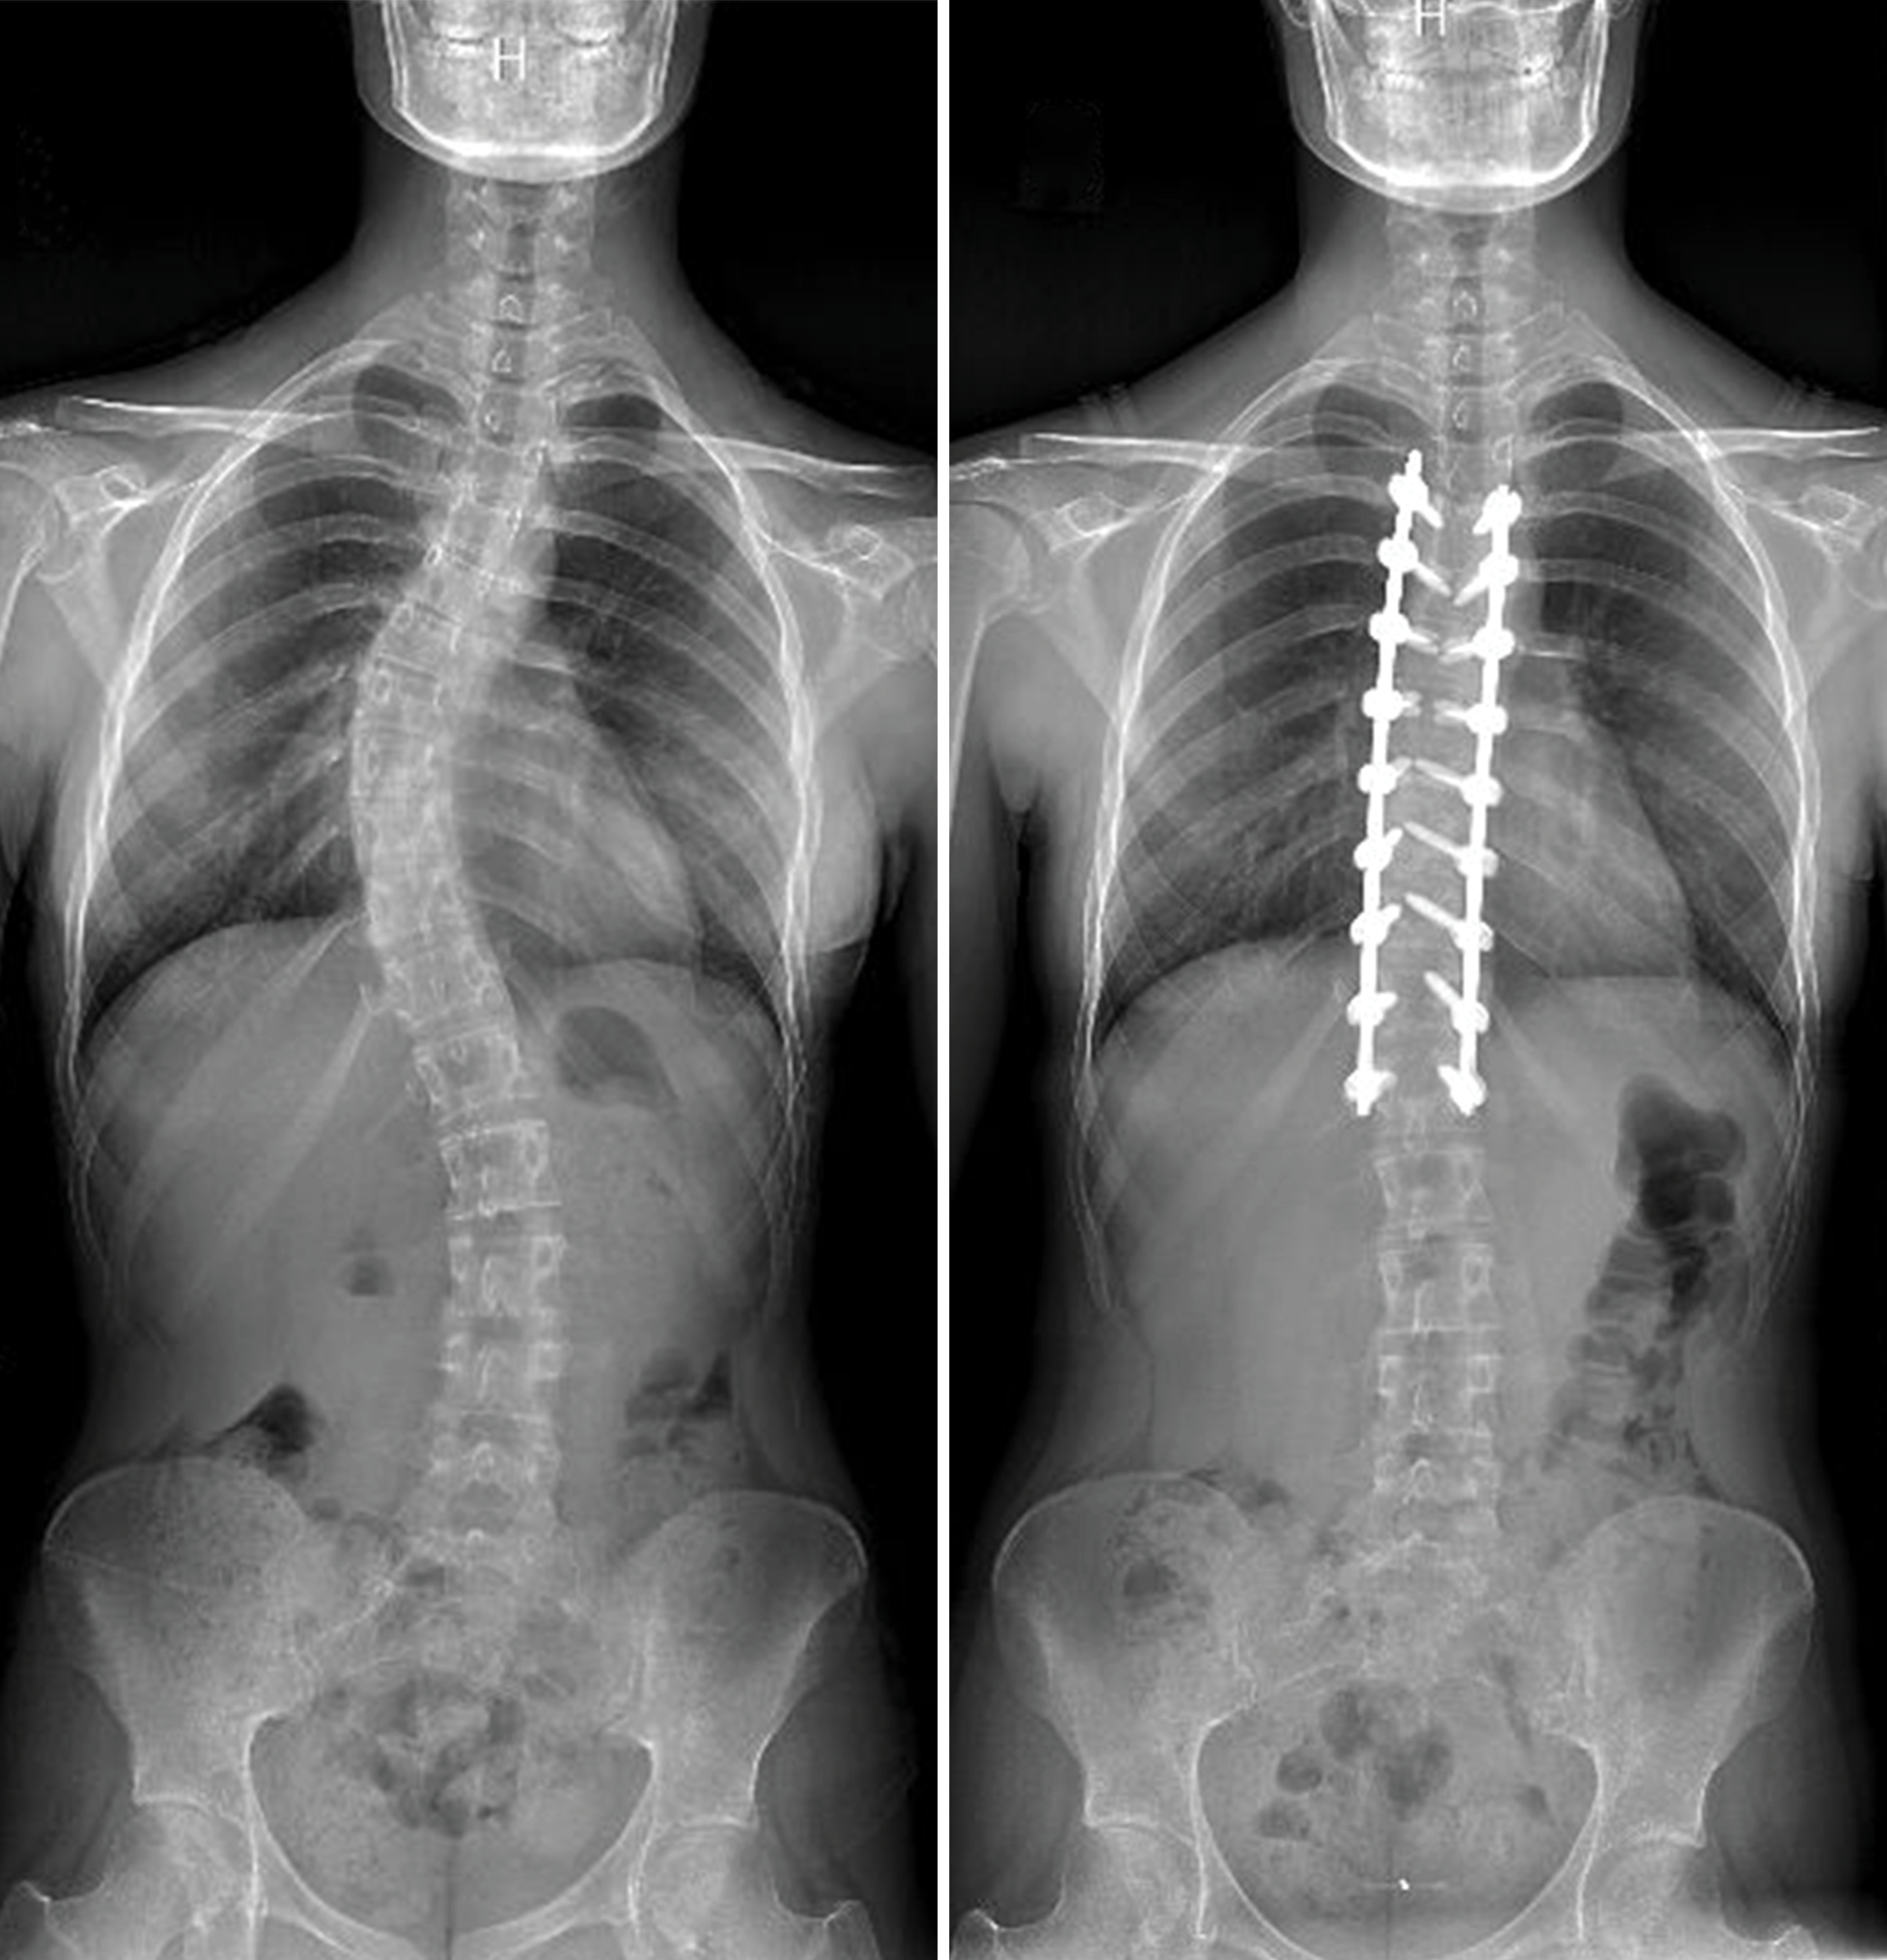

Kumar Kakarla, MD, a neurosurgeon at Barrow Neurological Institute who specializes in complex spine surgery for scoliosis and other spinal deformities, performed a spinal fusion on eight levels of Alexandra’s thoracic spine during the summer of 2022. Alexandra was 17 years old at the time and had received a diagnosis of scoliosis only a year before.

During X-ray imaging, Alexandra’s thoracic spine showed a 46-degree sideways curvature. “Anything below 25 degrees doesn’t really warrant treatment, because it doesn’t tend to get worse,” Dr. Kakarla said. “Anything about 45 to 50 degrees, we know from historical studies that it can still get worse into adulthood.”

Alexandra recalls the surgery lasting around four hours, during which Dr. Kakarla fused her spine from levels T4 to T12. Normally, intravertebral discs separate the bones of the spine, acting as shock absorbers and enabling movement. In a spinal fusion, the surgeon removes these discs and joins the vertebrae together with a bone graft to stabilize those levels of the spine.

Since Dr. Kakarla didn’t need to extend the fusion beyond the thoracic region of Alexandra’s spine, he was able to preserve most of her normal movement. “The less number of lumbar levels you involve in your spinal fusion, the less patients notice any loss of range of motion,” he explained. That’s because the thoracic region is already more rigid than the rest of the spine, due to its connection to the ribcage.

“I’m really pleased with Alexandra’s outcome,” Dr. Kakarla said. “We straightened her spine as much as we could, while still leaving all of the range of motion intact for her so that it wouldn’t interfere with her plans for her life. She did well and had a fantastic attitude.”